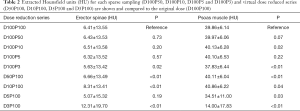

Mean MD was 6.41±13.55 HU for the erector spinae muscles derived from original dose images (D100P100). Sparse sampling derived mean MD showed no significant changes (P=0.57) down to 5% of the original projections (D100P5). For the psoas muscle, mean MD amounted 39.86±6.14 HU. No significant changes in mean MD of the psoas muscle were observed down to D100P5 (P=0.22) (Table 2 and Figure 2). Representative images of virtually lowered tube current and sparse sampling are shown in Figure 2.

Full table

The virtual tube lowering showed no significant (P>0.05) changes for the mean MD of the erector spinae at 5% of the original dose D5P100 (P=0.19) as compared to D100P100. However, mean MD derived from D50P100, D10P100 and D3P100 were significantly different as compared to D100P100 (P<0.01). In the psoas muscle, all virtually reduced tube current series showed significantly different mean MD as compared to the original dose.

The comparison of corresponding sparse sampling and virtually tube reduced series (D100P50/D50P100, D100P10/D10P100, D100P5/D5P100 and D100P3/D3P100) is shown in Table 3. The 50% and 10% reduced series of the psoas and the 5% reduced series of the erector spinae MD did not differ significantly from each other (P>0.05) (Figure 3).

The Signal-to-noise ratio (SNR) for each virtually tube reduced series is shown in Table 4. In the erector spinae the SNR did not reveal significant differences for the sparse sampling series down to 5% (D100P5) of the original dose (P=0.08). A high ICC was given between the two readers in both muscle compartments (ICC =0.98, P<0.01).